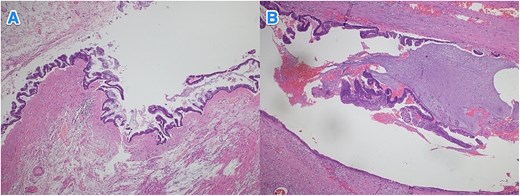

Light microscopy images of the appendix show low-grade dysplastic epithelium on the surface of the appendix (hematoxylin and eosin stain; 10×).

Light microscopy images of the appendix (A, B) show low-grade dysplastic epithelium on the surface of the appendix (hematoxylin and eosin stain; 4×).